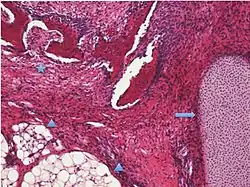

| Surface epithelial-stromal tumor | Serous tumor | 25% | 18.5% | Benign serous tumors of the right ovarian cyst are thinwalled unilocular cysts that are lined by ciliated pseudostratified cuboidal or columnar epithelium.[9] |

|